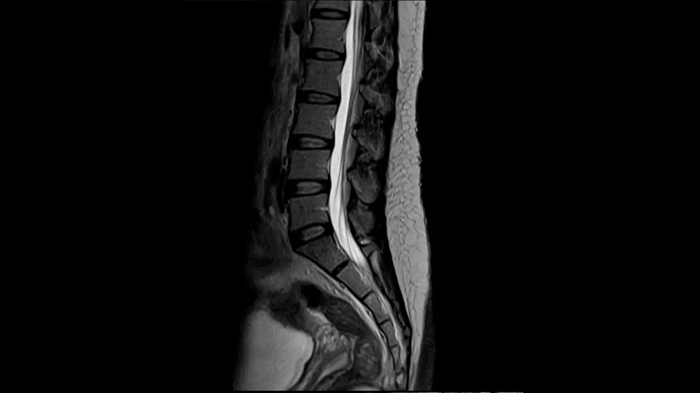

T2 TSE

Ideal depiction of the lower spine with T2 TSE imaging with the use of the Spine Coil.

Deep Resolve Gain & Sharp

0.4 x 0.4 x 4.0 mm2

TA 3:24 minutes

MAC-ID: 7aaaa0215. Image Credit: Siemens Healthineers